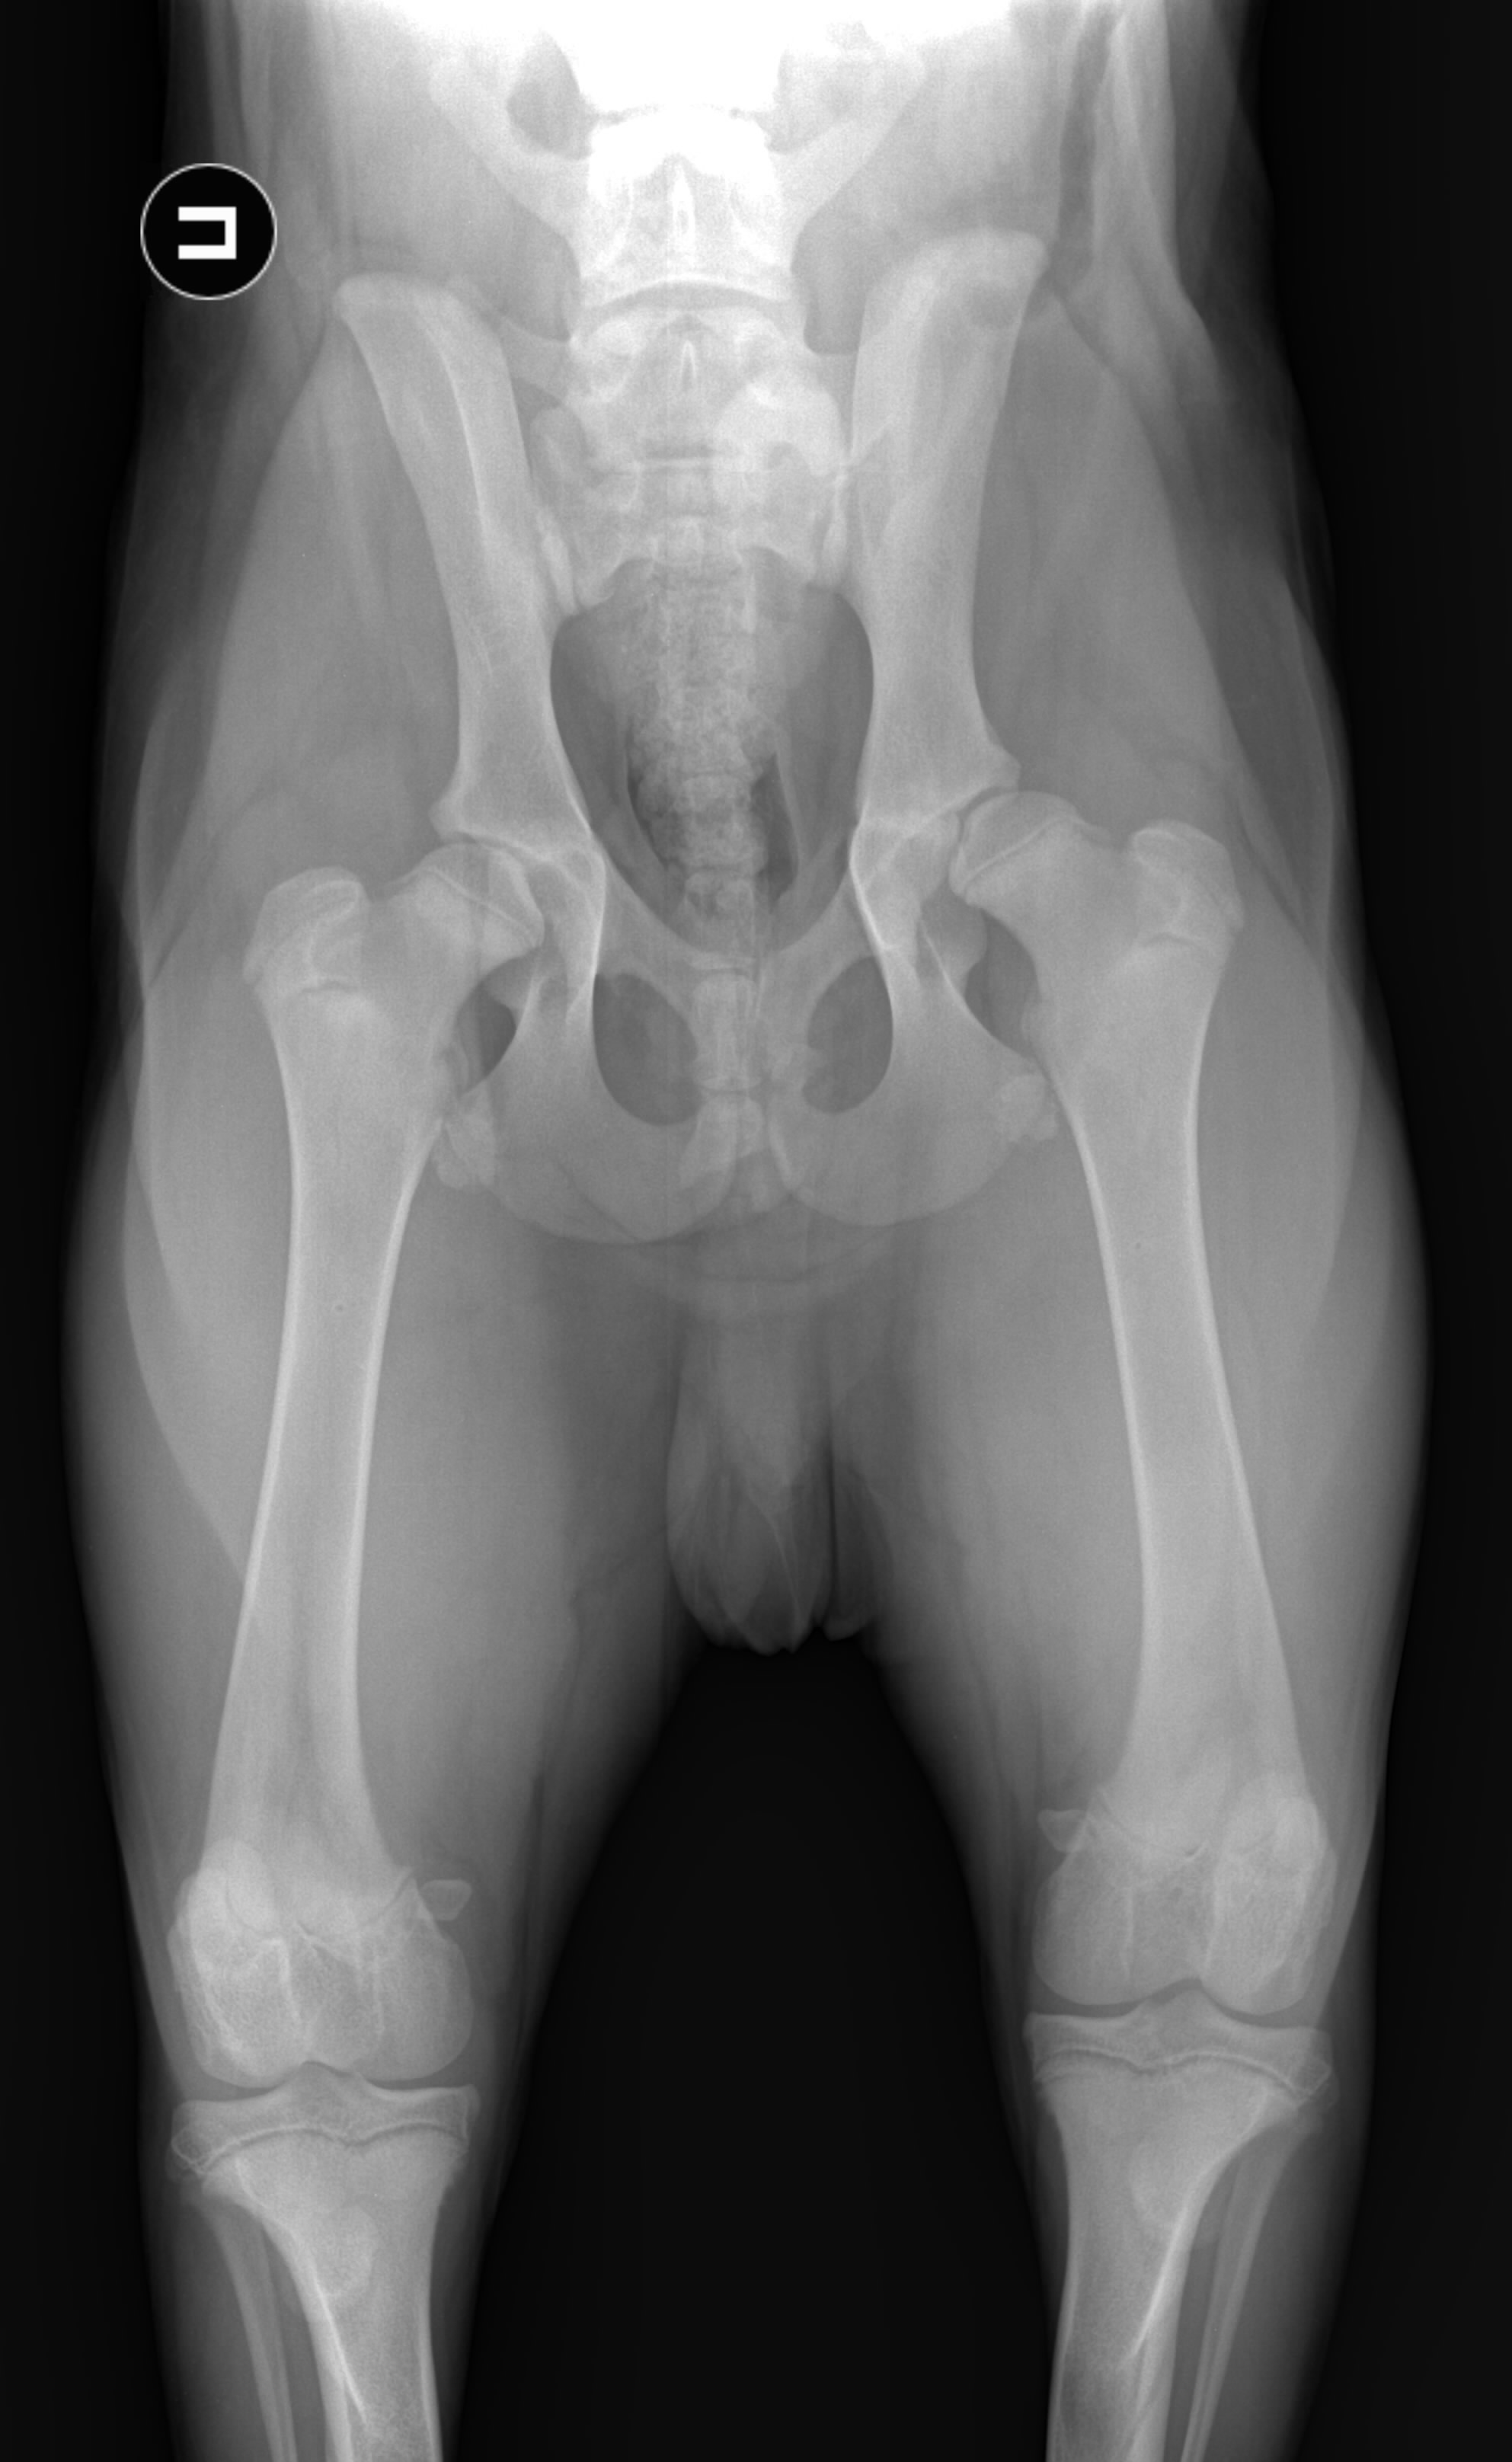

Собаки — не единственный вид, у которого наблюдается дисплазия тазобедренного сустава. Это также может произойти у кошек, хотя и не так часто, как у собак. Мейн-куны — это порода кошек, которая чаще всего поражается.

Пожилая кошка с дисплазией тазобедренного сустава

Белыми стрелками обозначено большое количество стула в толстой кишке указанной кошки с дисплазией тазобедренного сустава. Этой кошке больно сидеть на корточках, чтобы опорожнить кишечник, в результате чего у нее сильно запор.